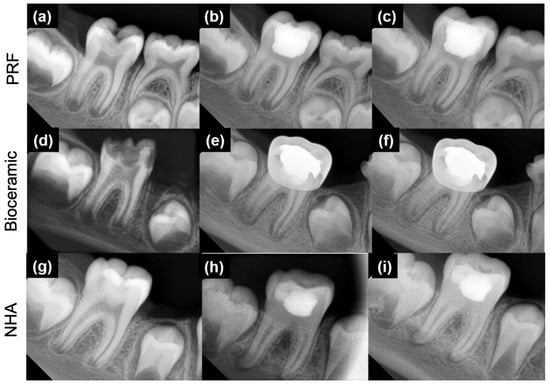

| Criteria/Group | MM-MTA (G1) | Nano-Hydroxyapatite (G2) | PRF (G3) | Statistical Analysis |

|---|---|---|---|---|

| Age (years) | 8.6 ± 2.0 | 8.8 ± 1.8 | 8.8 ± 2.1 | p = 0.911 |

| Sex females (%) | 11 (55) | 10 (50) | 9 (45) | p = 0.819 |

| Apical closure complete (6 months) (%) | 5 (25) | 3 (15) | 4 (19.04) | p = 0.726 |

| Apical closure complete (12 months) (%) | 10 (50) | 11 (55) | 12 (60) | p = 0.817 |

| Canal obliteration (6 months) (%) | 3 (15) | 4 (20) | 0 (0) | p = 0.111 |

| Canal obliteration (12 months) (%) | 7 (35) | 9 (45) | 1 (5) | p = 0.014 * |